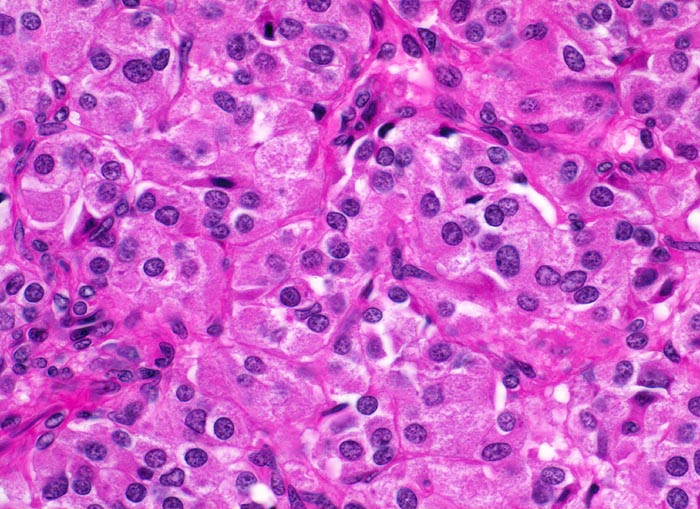

Das MTC metastasiert primär in die lokoregionären Lymphknoten. Bei 15% der Patient*innen liegen zum Zeitpunkt der Diagnose bereits Fernmetastasen in Lungen, Leber oder Knochen vor. Histologisch sind die Tumoren meist solide und bestehen aus monomorphen polygonalen und spindeligen Zellen (> 3821). Die Zellkerne zeigen das typische Pfeffer und Salz Chromatin neuroendokriner Zellen. Das Stroma enthält in ca. 50% der Fälle Amyloid.

• Tumorzellen mit überwiegend monomorphen Zellkernen mit feinkörnigem Pfeffer und Salz Chromatin (Merkmal endokriner Zellen). Nukleolen sind nicht prominent. Reichlich eosinophiles Zytoplasma.